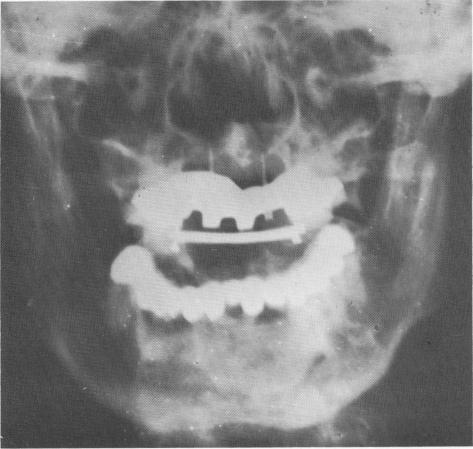

Fig. 15-20. A posteroanterior view of the case showing the full arch lower fixed denture as well as the maxillary anterior narrow ridge implants, template, and bar. The acrylic teeth cannot be noticed on the radiograph.

1 Posteroanterior view of maxillary narrow ridge implant, template, bar